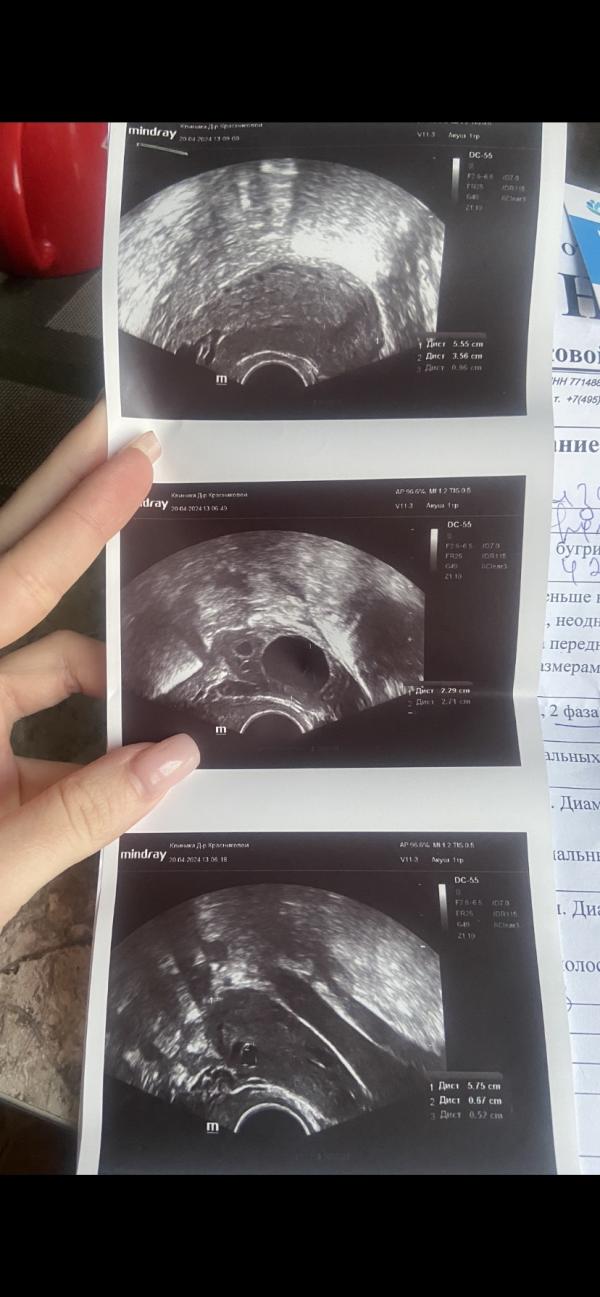

20.04.2024 : иду к гинекологу , делают узи ( ПРИКРЕПЛЮ ФОТО ) , фолликул 23 мм - овуляция .. гиня сказала бежать домой с мужем сейчас же, любить друг друга и по возможности сделать укол ХГЧ 10.000, а также начать пить дюфастон